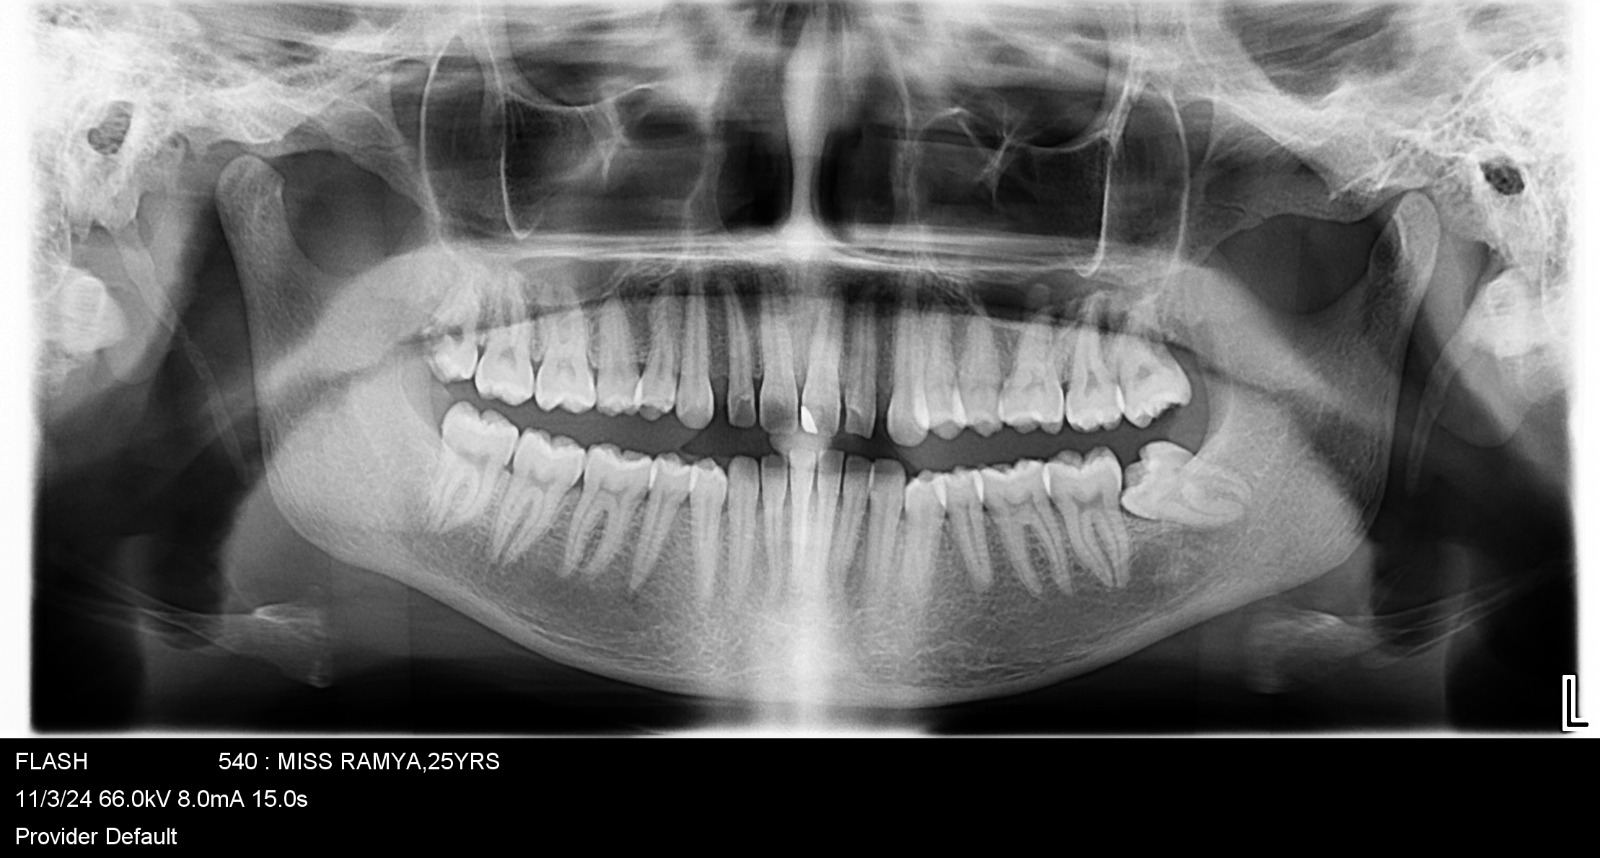

Images Of Dental Treatment Servcies Done At Our Hospital